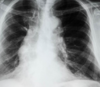

A

Consolidación alveolar

How well did you know this?

1